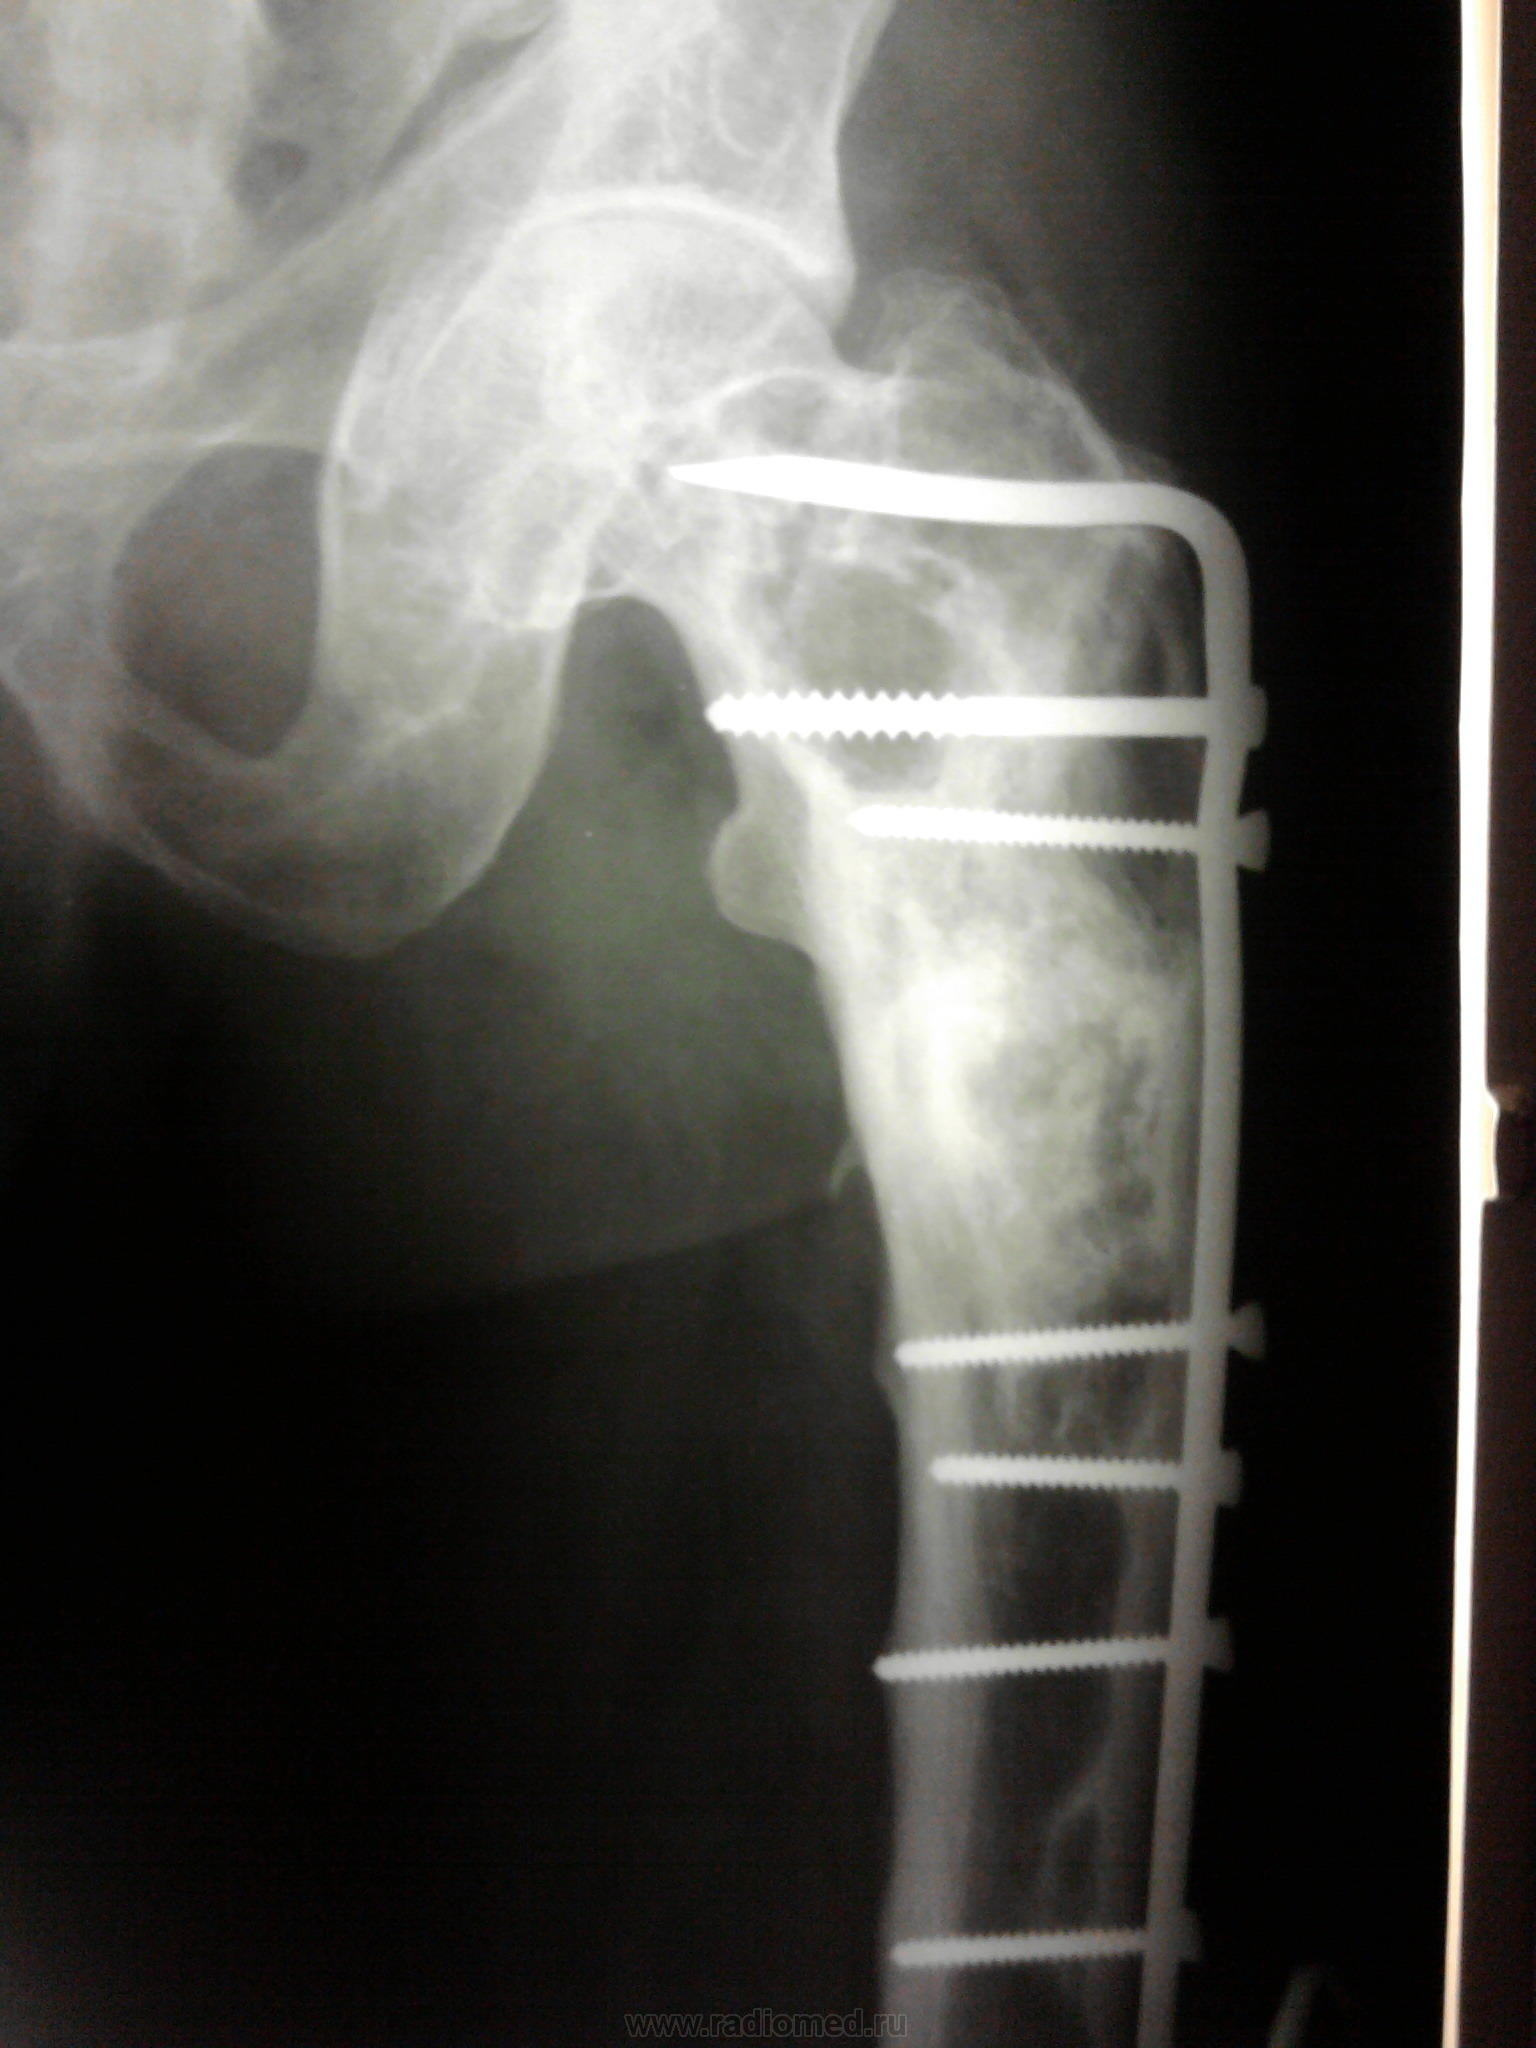

Двухсторонние литические очаги, с четкими, местами склерозироваными контурами. Старый консолидированый перелом левой бедренной кости, после металлоостеосинтеза металлической пластиной. Миеломная или мтс проявили бы себя более агрессивной деструкцией.

tatyana, Вам "зачет"! Здесь действительнро болезнь Реклингхаузена. Наблюдаю данного пациента лет 7. За это время его патологический перелом левой бедренной кости так и не срастается, приобретая все более атрофичный вид в виде перетяжки на уровне излома, потому и держат с металлом до сих пор. Классическая "пастушья палка". Справа в теле подвздошной кости и (менее выраженно) ближе к задней нижней ости, а также в большом вертеле также имеются литические очаги, относительно стабильные за время наблюдения.

"самоуверенность дилетантов - предмет зависти профессионалов"